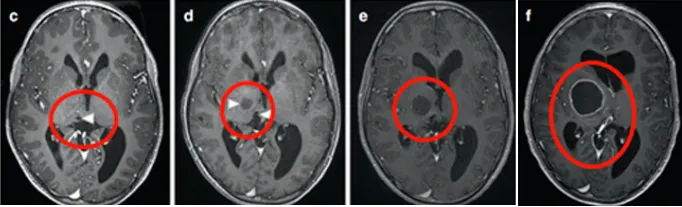

症状不严重,手术风险太大,做完可能比现在更差,医生评估不具有手术指征。然而,肿瘤一直长大,而且长出了很多小的囊肿。同侧内囊(负责人体肢体运动)也向前外侧移位,导致马修从左上肢震颤到急性偏瘫。

为了治疗多发囊肿,他们找到INC鲁特卡教授植入ommaya囊并在超声引导下将导管插入肿瘤囊性成分。MRI显示囊性占位解除,脑室慢慢恢复正常。

4个月后,马修的偏瘫没有改善,鲁特卡教授又为其行经胼胝体半球间入路及肿瘤切除术,顺利切除了肿瘤。术后,马修的偏瘫改善,生长和智力发育都正常。